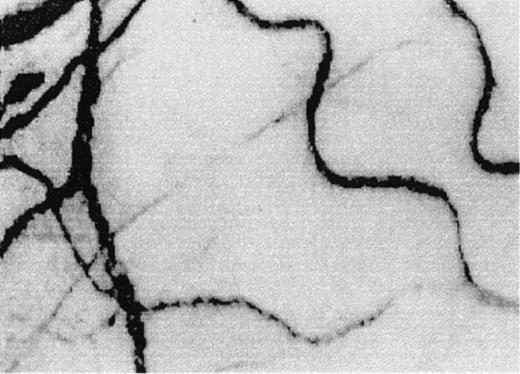

Two frame-captured steady-state images of the conjunctival microcirculation showing additional microvascular abnormalities.

Optical magnification, × 4.5; onscreen magnification, × 125. (A) Inadequate vascularization (avascularity), two types of comma signs (CS1 and CS2), blood sludging (S), and the intermittent boxcar (sluggish) blood flow phenomenon (BC) are present. (B) Another view of comma signs (CS1), blood sludging (S), and the boxcar blood flow phenomenon (BC).

Sludging of blood and the presence of comma signs in the vessels of the bulbar conjunctiva in SCD patients were first noted decades ago by Knisely et al10 and Paton,11,12respectively. Blood sludging and comma signs are caused by stagnation of blood flow in conjunctival vessels resulting in extremely slow or no blood movement; sludging can be seen when midsized to large-sized vessels are compacted with red cells (“S” in Figures1B-D and 2), while comma signs are seen as short columns of stationary red cells in small obstructed vessels (“CS1” and “CS2” in Figure 2, for the 2 unique shapes of comma signs observed). When blood flow in the small conjunctival vessels (mostly in arterioles and sometimes small venules) is sluggish or intermittent, the boxcar blood flow phenomenon—so called because of its unique railway boxcar aerial appearance—results (“BC” in Figures 1B and 2). Pioneering SCD investigators8,9,13-19have used the conjunctival microcirculation in their research, speculating that the abnormalities were of significance not only because they could be detected but that they might reflect functionally and morphologically more deleterious or pathological microvascular events in the jeopardized tissues. These historical studies were based on slit-lamp biomicroscopy via 35-mm photography, and the results were mostly descriptive and rarely quantified.8-19